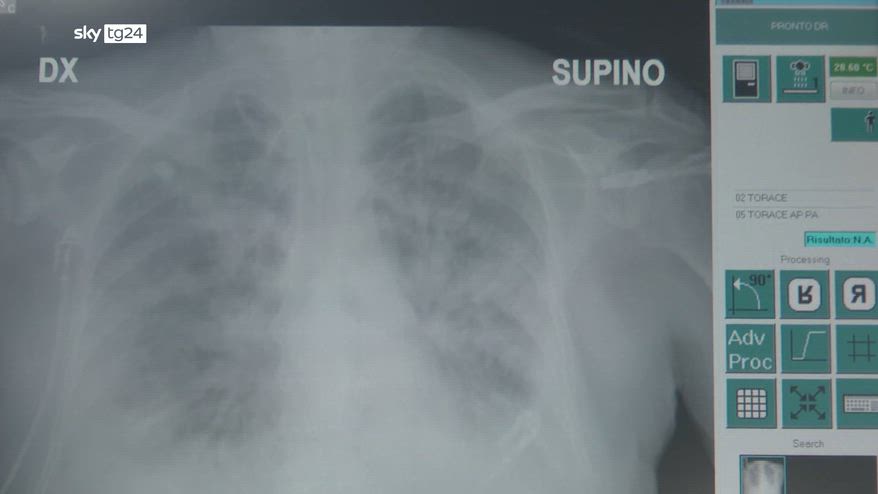

La polmonite interstiziale è un tipo di infezione che colpisce la zona che circonda gli alveoli polmonari e i vasi sanguigni. È qui che avviene lo scambio di ossigeno, quando c'è un'infiammazione l'ossigeno fatica a passare nel sangue e questo può generare problemi anche gravi. "Ci sono più tipi di polmonite interstiziale, ci sono le polmoniti interstiziali di origine infettiva che sono dovute a virus, a batteri e poi virus, come ad esempio il SARS-COV 2." Fra le persone ricoverate la mortalità arriva al 10-15%, nonostante gli antibiotici, se si arriva a dover intubare il paziente il rischio sale al 50%. Il vaccino è la prima forma di protezione. "Se si prevengono queste infezioni i soggetti che abbiano già delle patologie polmonari, tipo ad esempio la fibrosi polmonare idiopatica, anche questi soggetti particolarmente questi soggetti sono una categoria che si avvale della diciamo copertura, dal rischio di avere una prognosi infausta." Batteri, virus di stagione, malattie preesistenti, le cause possono essere molte, tra queste il Covid che lo ha contratto e presenta esiti cicatriziali, deve stare attento. "Chiaramente questa persona non è più a rischio di avere una polmonite intestiziale, ma se la presenta è chiaramente più fragile, quindi è più a rischio di avere complicanze, così come sono più a rischio di avere complicanze, i soggetti anziani, gli immunocompromessi, i cardiopatici, i soggetti che hanno il diabete." Uno strumento utile per fare un controllo in casa è il saturimetro che misura la quantità di ossigeno nel sangue, la soglia di allarme è il 92%.